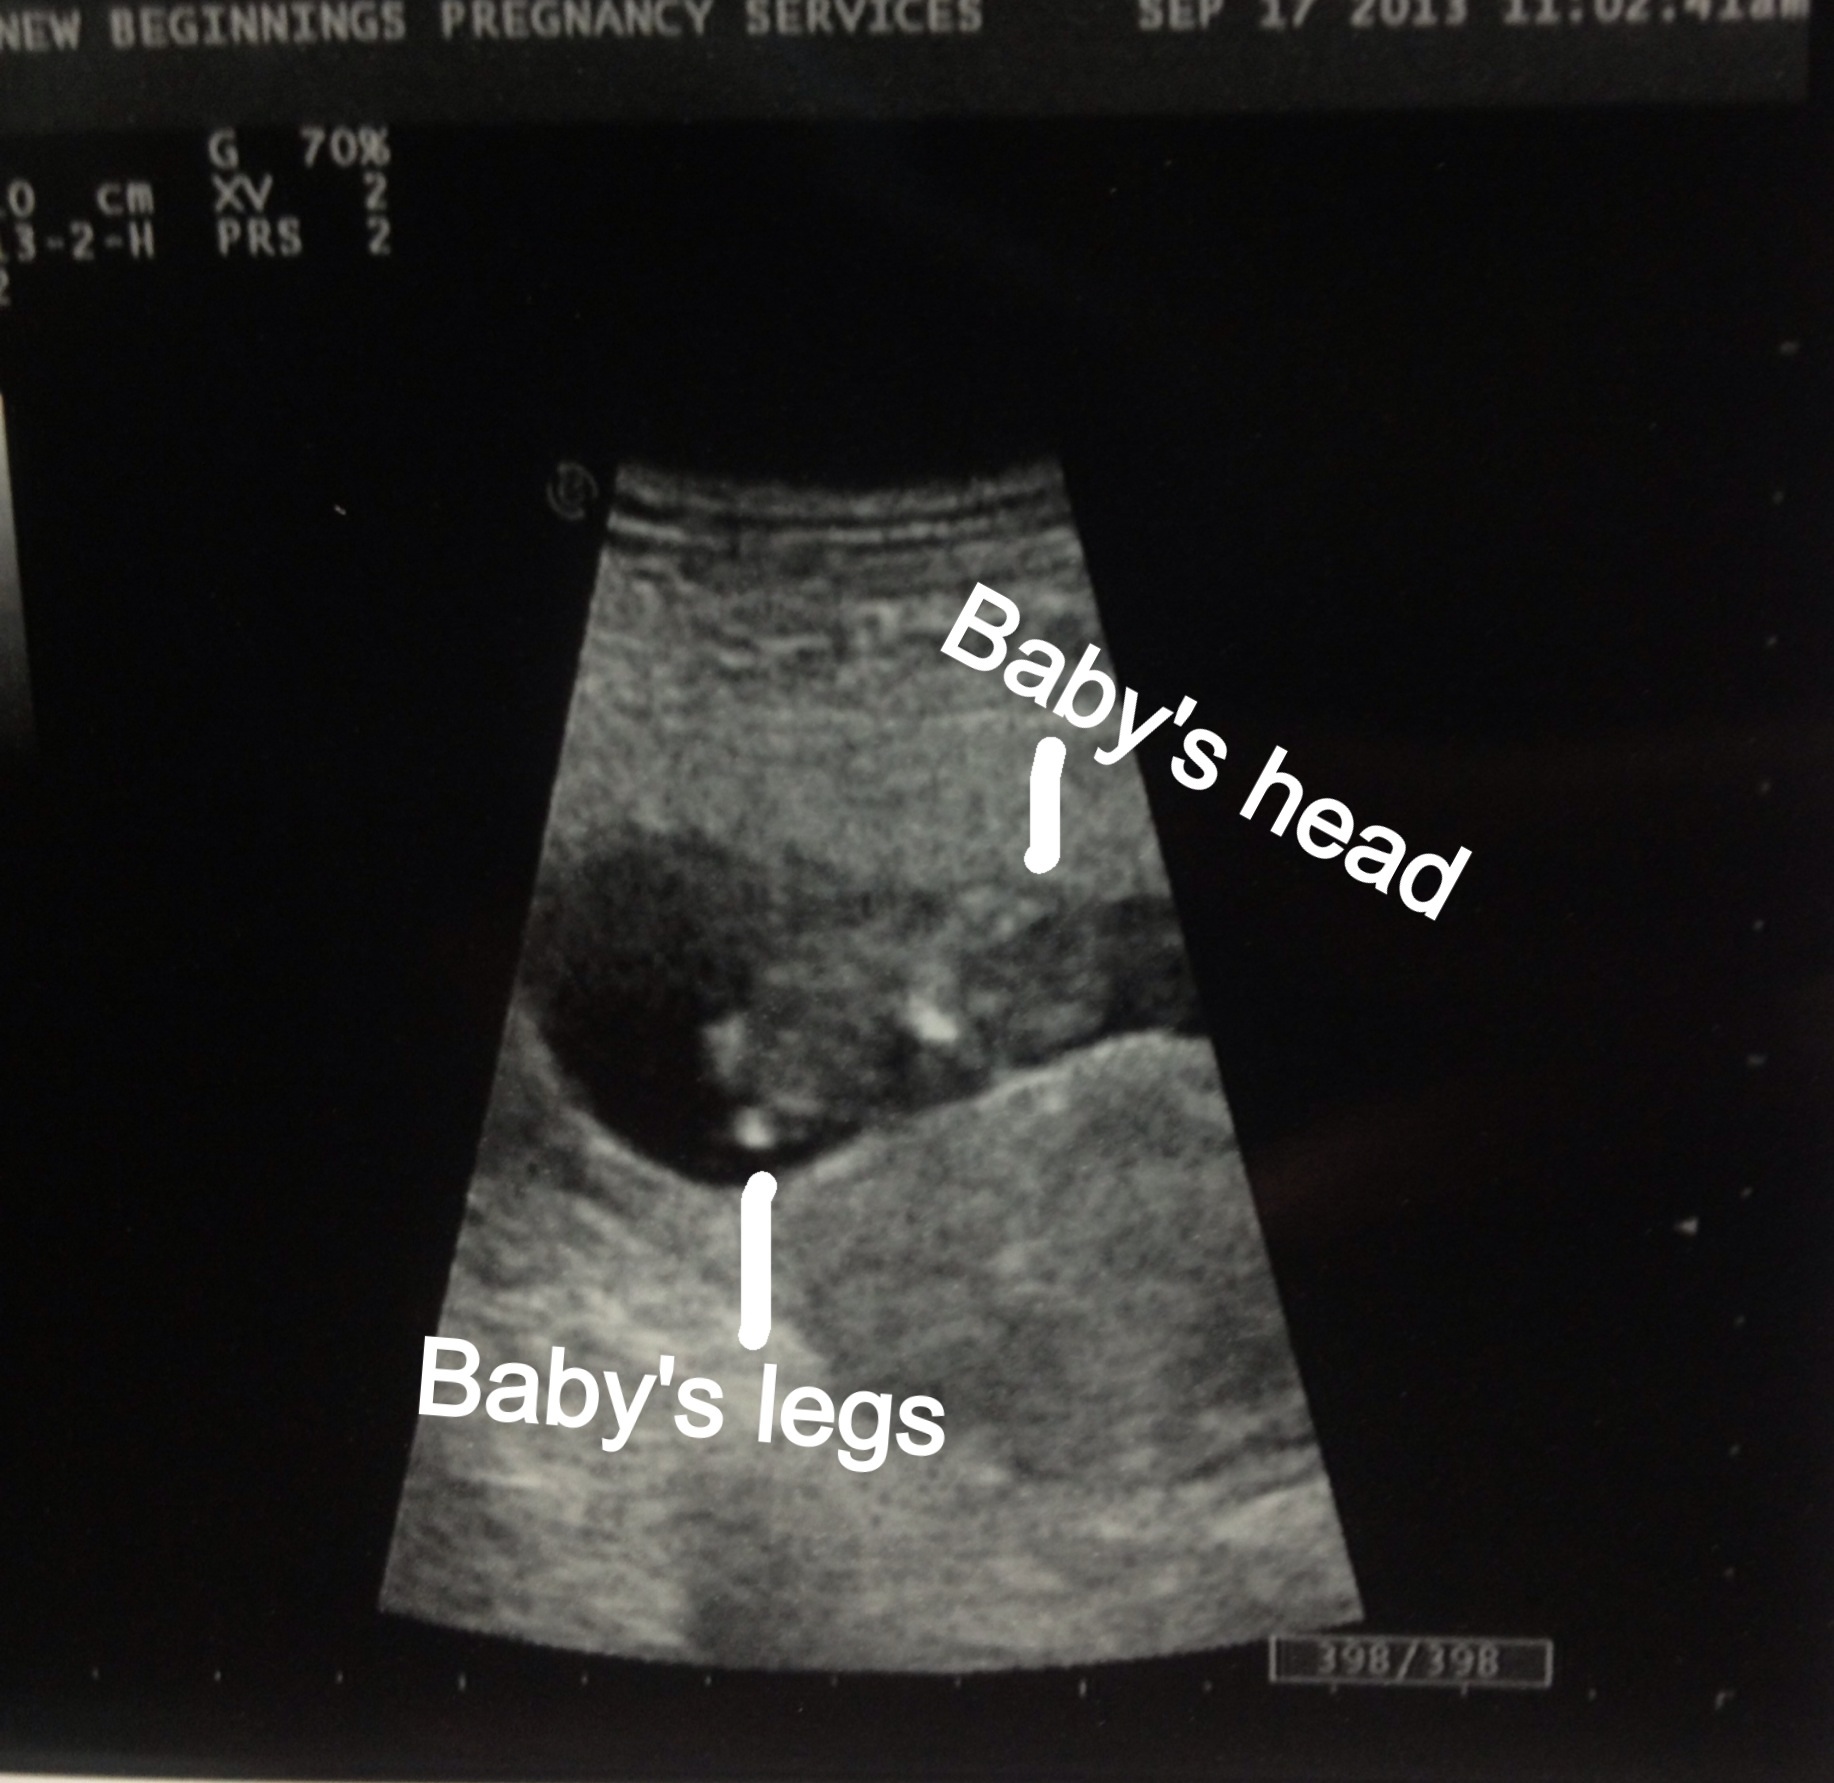

Have to show off my US pic!

Officially passed my MC milestone and am so relieved. Baby was wiggling all around for us and had a HR of 164. Measured 9w5d.

The pic has been labeled since I sent it to ppl who have no idea how to find the baby in the pic.

• Oh yay a beautiful little bean!!!! Congrats! I can see its little feet awwww!